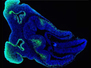

Delirium, seizures, and deep coma. These are all signs of cerebral malaria, one of the most severe consequences of being infected with the parasite Plasmodium falciparum. How this parasite causes cerebral malaria is still unclear. Researchers modelled this condition in mice using two types of Plasmodium; one that causes cerebral malaria and one that doesn’t. Using fluorescent microscopy they found both types caused the immune cells, T lymphocytes (green), to accumulate alongside blood vessels (red) in the brain. However comparing the behaviour of T cells in these brains revealed those in brains infected with parasites that cause cerebral malaria (pictured) behaved quite differently. They were arrested, moving more slowly and not venturing as far. More digging is now needed to find out how this uniquely sluggish behaviour contributes to the detriment of brain function in cerebral malaria.